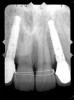

Figure 1  Pretreatment radiographs revealed convergent roots for the right canine and right central.

Figure 1

Periapical radiographs were taken to help determine the mesial-distal inclinations of the adjacent tooth roots (Figure 1). The radiographs revealed a serious issue, convergent roots for the right canine and right central, which eliminated that area as a potential implant-receptor site. The space between the left central and canine teeth was minimal, although the roots were relatively parallel. Clinical examination (manual palpation of the root eminences superiorly to the vestibule on the right side) confirmed the root convergence (Figure 2A). The flat, wide zone of the keratinized tissue and lack of interdental papilla was evident for the missing right lateral incisor. There was a marked difference in clinical appearance for the left lateral, which could impact the eventual plan of treatment (Figure 2B). Other significant clinical findings included bilateral facial bone concavities, which existed as a result of the congenitally missing tooth roots. As a diagnostic cue to the underlying bone topography, it is important to follow the demarcation between attached and unattached gingival tissue, and note the crestal width of the available keratinized tissue (Figure 2C).